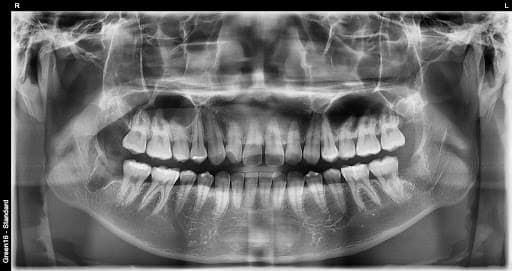

Aql tishini olish shartmi?

Og'riq bo'lmasa ham milka ichida yallig'lanish, chirish, tish qatori buzilishiga sabab bo'lishi mumkin. 3D CT bilan aniq diagnostikadan so'ng zaruriyat aniqlanadi, oldindan olmasa o'tkir yallig'lanish, qo'shni tish shikastlanishi, jag' bo'g'imi muammolari yuzaga kelishi mumkin. Yosh bo'lgan sari tezroq tiklanish va asorat xavfi kamroq bo'ladi.

Murakkab aql tishini ham olish mumkinmi?

Ha, mumkin. Yonsei Ona Stomatologiyasi boy tish olish tajribasi va universitet kasalxonasi darajasidagi murakkab tish olish tizimiga ega. Gorizontal ko'milgan, to'liq ko'milgan va boshqa stomatologiyalarda katta kasalxonaga yuborilgan qiyin holatlar ham 3D CT aniq diagnostikasi bilan xavfsiz olinadi.